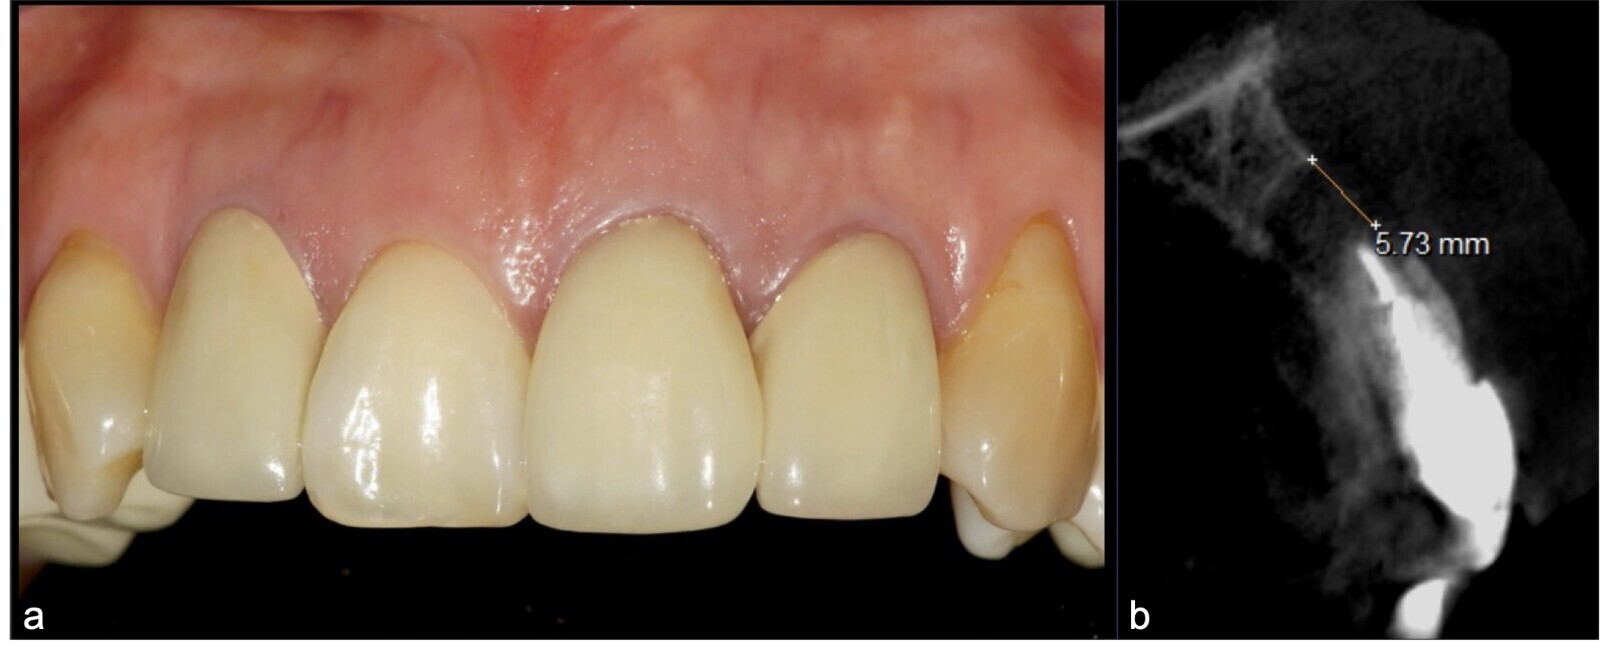

Figura 11. Fotografía frontal en la que el paciente presenta línea de sonrisa baja, y coronas de porcelana definitivas en incisivos superiores.

Figura 12. Fotografía frontal: restauraciones cerámicas definitivas, con ausencia de lesiones fistulosas (a). Corte sagital de TCCB pieza 2.1: imagen hipodensa compatible con lesión periapical osteolítica de aproximadamente 5.73 cm de diámetro, con compromiso de la tabla vestibular y palatina (b).